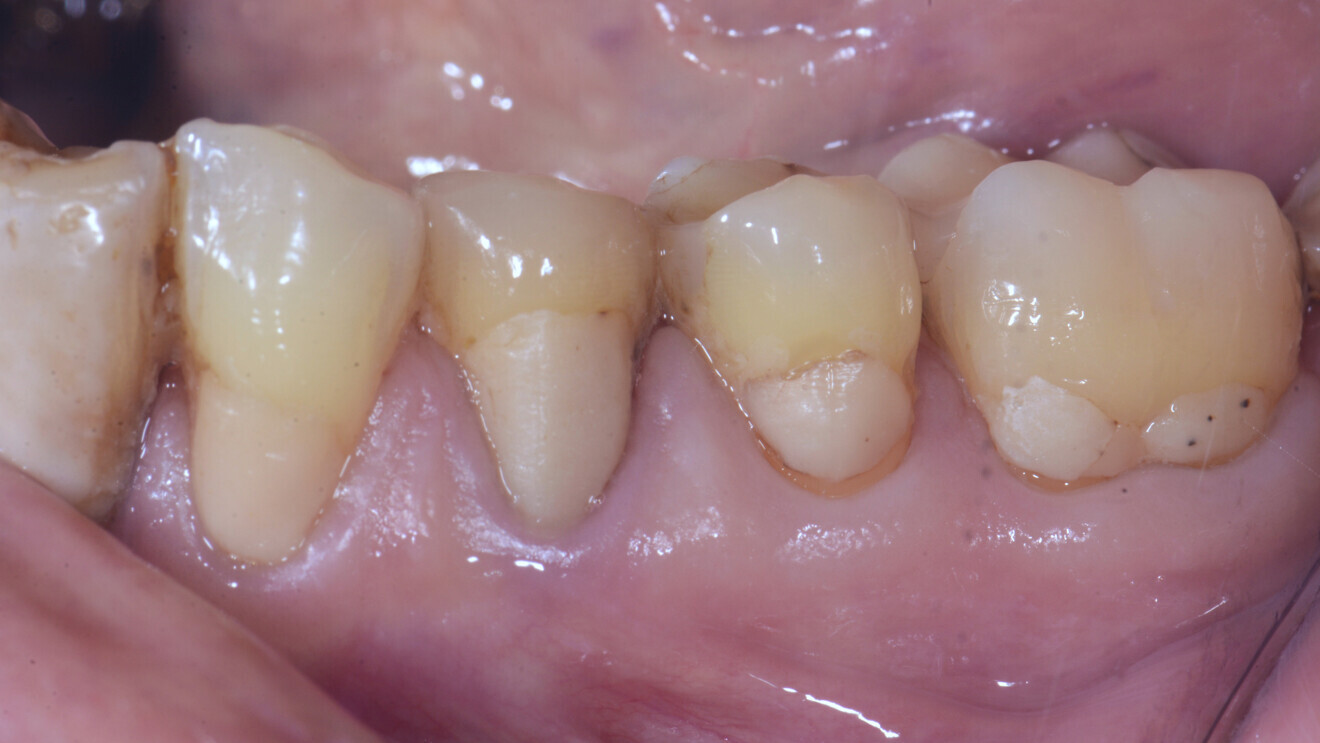

En ce qui concerne les verres hybrides, les seules données disponibles sont des études randomisées qui ont comparé ce matériau avec les résines composites dans les lésions non carieuses (Fig. 4).

Fig. 4a : Dans les études cliniques randomisées et contrôlées, les verres hybrides montrent des résultats prometteurs pour la restauration des lésions cervicales. a) Lésion cervicale non carieuse, avant traitement,

L’étude la plus intéressante concernant les caries radiculaires est celle qui a évalué un verre hybride (EQUIA Forte, GC) par rapport à des restaurations en résine composite (Filtek Supreme XTE, 3M) pour le traitement de lésions radiculaires non carieuses présentant une dentine sclérotique chez 88 patients d’âge moyen et plus avancé (50 à 70 ans).10

Une évaluation de la survie, de la qualité et des coûts de 92 restaurations, mises en place sans aucune préparation mécanique (ayant finalement entraîné des taux d’échec annuels élevés pour les deux groupes) a été réalisée sur une durée de 36 mois. La qualité des restaurations a été évaluée après 1, 18 et 36 mois selon les critères de la Fédération dentaire internationale (FDI). Les coûts ont été évalués à l’aide d’une approche reposant sur le microcosting (comptabilisation du temps utilisé pour la mise en place du matériau) et, pendant le suivi, sur les prestations de l’assurance maladie obligatoire en Allemagne. Après 36 mois, une perte totale de rétention a été constatée pour 17 verres hybrides et 19 résines composites, et une perte partielle pour 5 verres hybrides. Les coûts liés aux verres hybrides étaient nettement inférieurs, tant au début de l’étude (verres hybrides : 32,57 euros [écart type 16,36 euros] par rapport aux résines composites : 44,25 euros [écart type 21,40 euros]) et sur toute la période de suivi (verres hybrides : 41,72 euros [écart type 25,08 euros] par rapport aux résines composites : 51,60 euros [écart type 26,17 euros]).